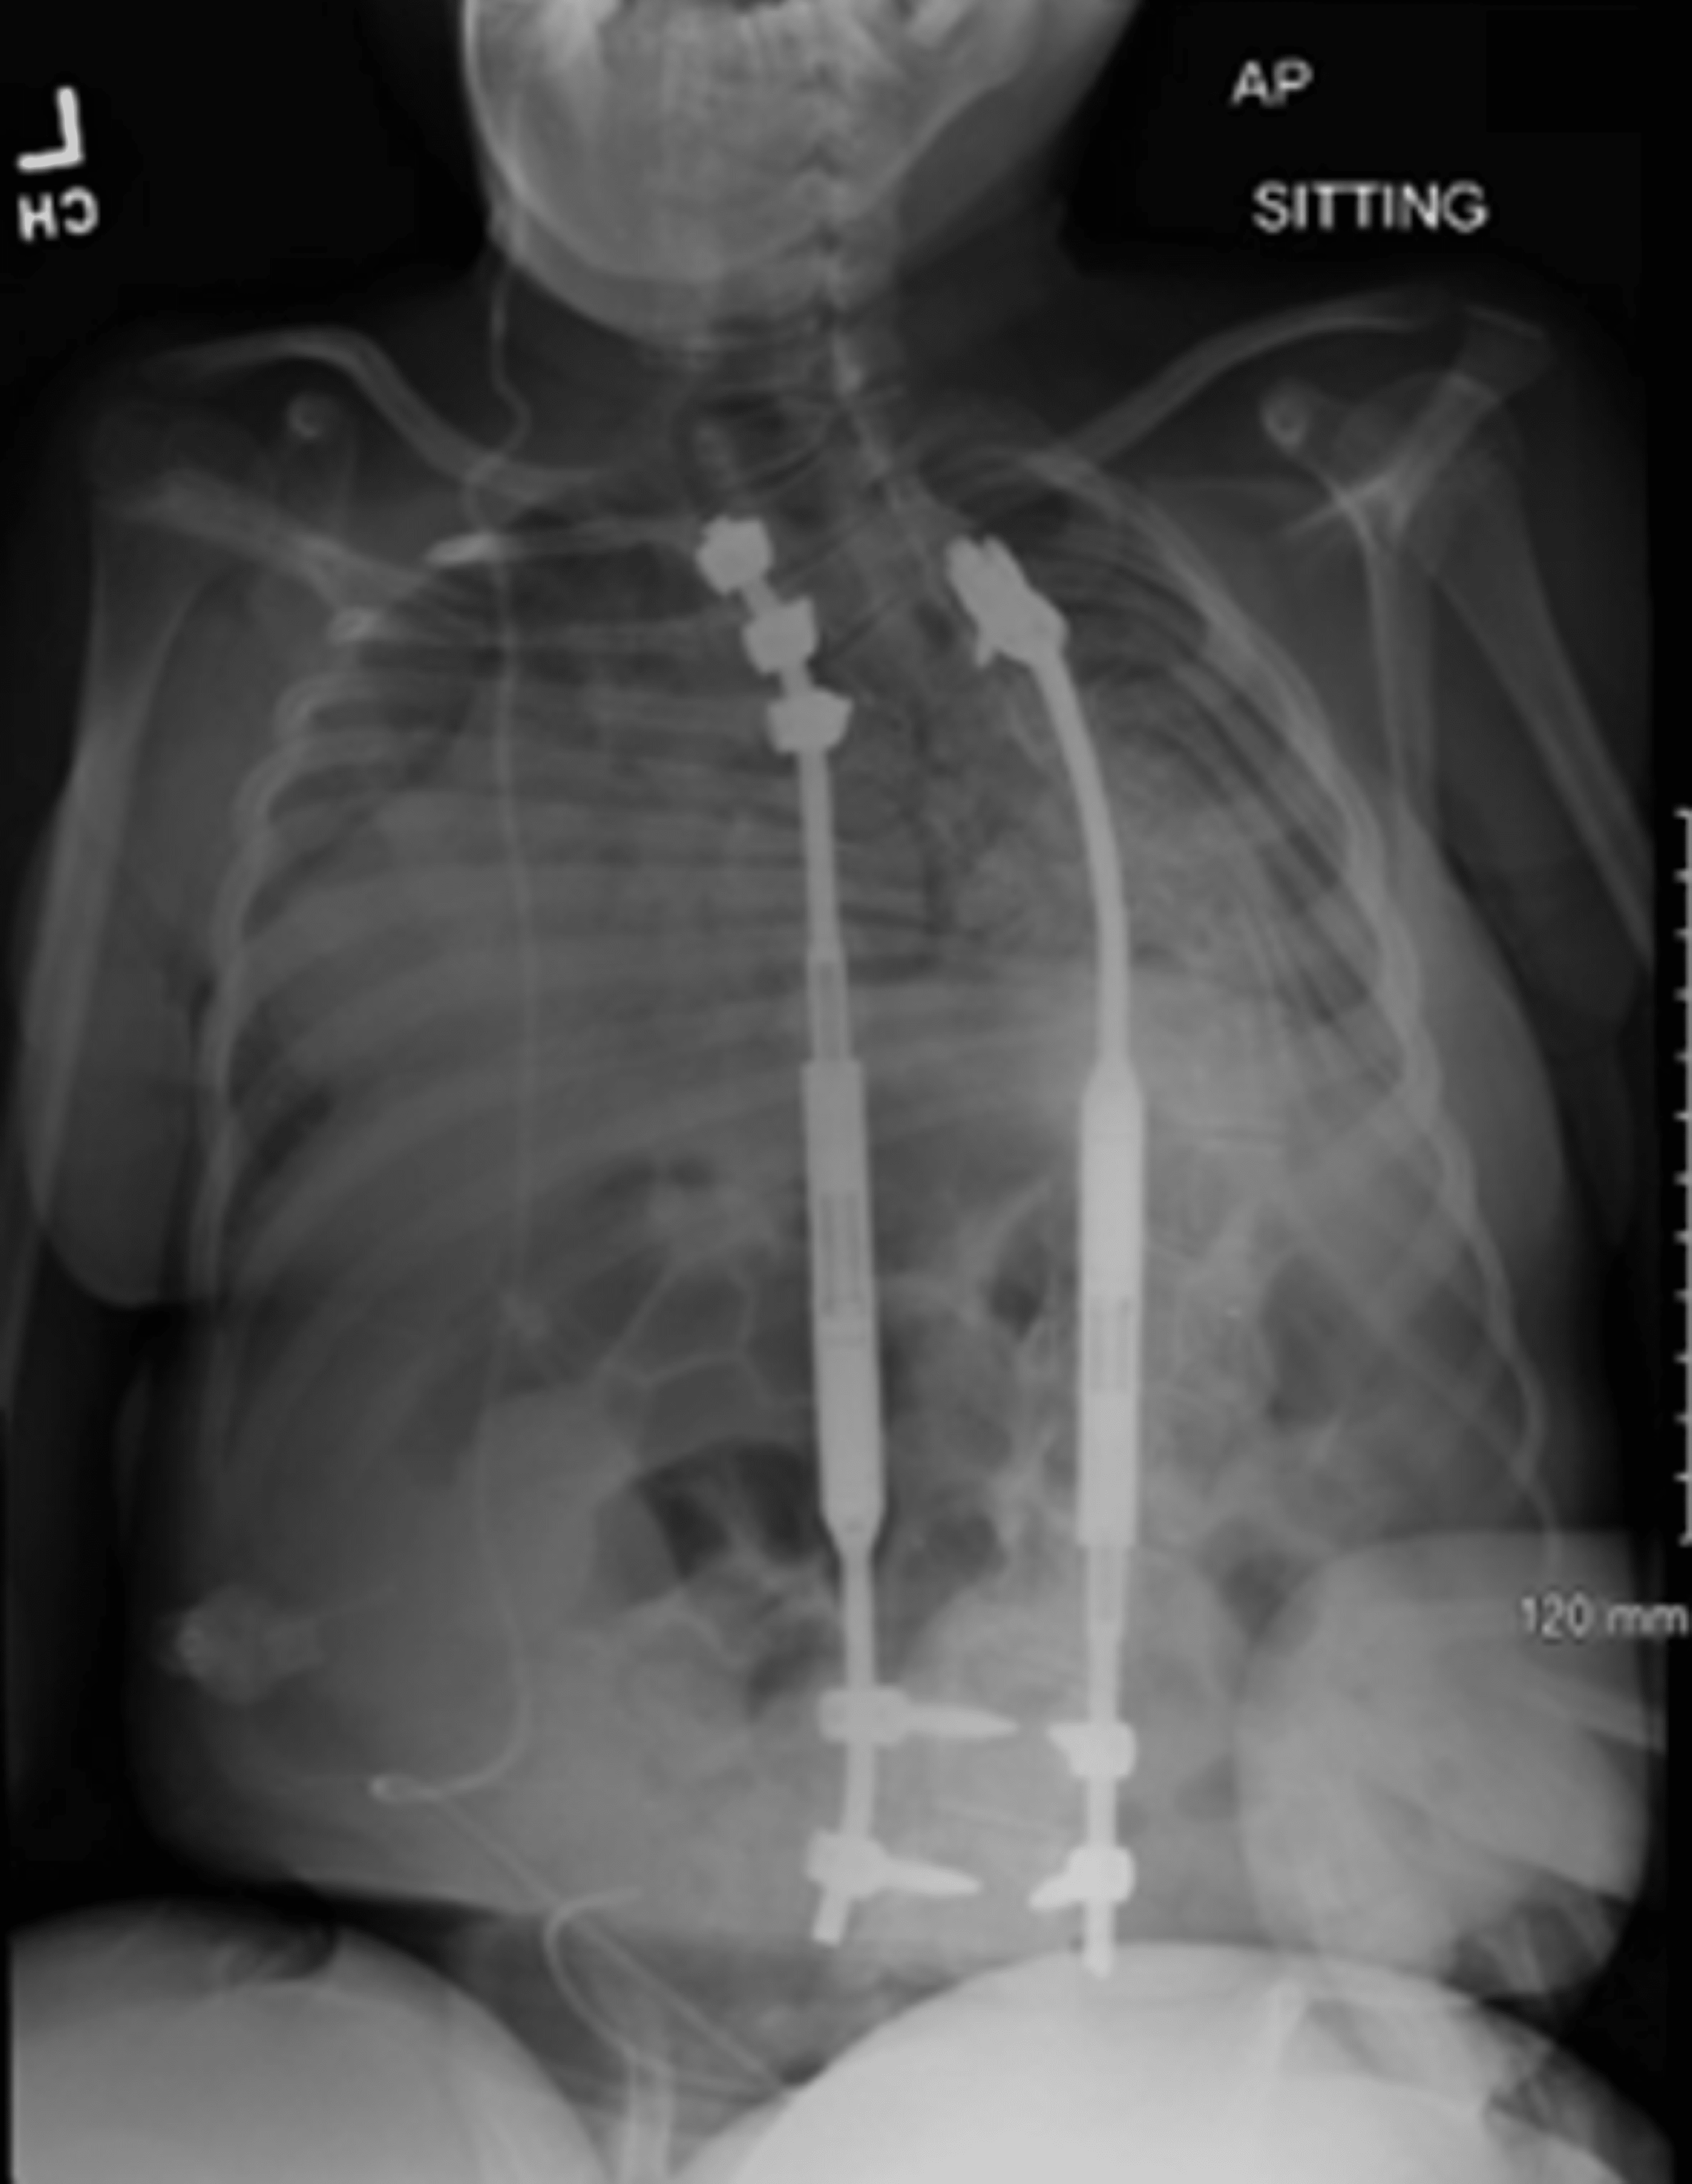

From radiopaedia.org

Neuromuscular scoliosis and MAGEC rods Image Magec Growing Rods Mri Safety Its magnets will create a substantial artifact, however, obscuring most of the chest. Magec growing rods have not been approved for use in magnetic resonance imaging (mri) (both the mri and the magec growing rods are. Magec Growing Rods Mri Safety.